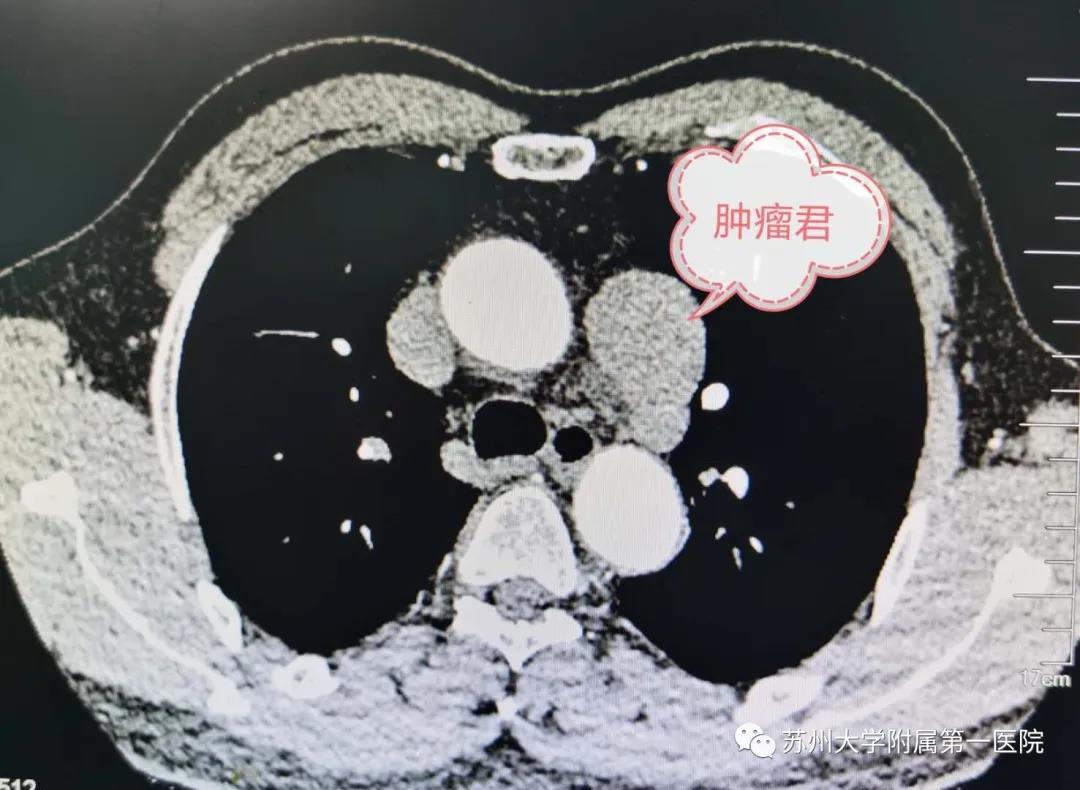

没想到我这么大岁数,切掉一个肺叶的十年后,再次做这么复杂的手术还这么顺利。 D大爷今年72岁,10年前曾行左肺上叶切除+淋巴结清扫术,手术标本病理为腺癌,术后给予了四次化疗。当时的胸部CT即可见右肺上叶小结节影,术后定期复查,病灶缓慢增大,一度略有缩小,此后再次逐渐增大。结合患者一直随访的影像学资料,杨如松院长考虑为右上肺新发恶性肿瘤。 2015年胸部CT 2020年胸部CT 虽然患者及其家属手术的意愿非常强烈,但此手术难度较高,原因在于: 1.患者年龄较高,手术风险大。 2.患者10 年前肺癌手术切除左边肺的一半,肺功能丧失较多。 3.病灶在右上肺的深部,切除有一定的难度。 为了保证患者术后的生活质量,我们不能够做肺的楔形切除这样的简单肺手术,而需要行肺段的切除。 EDDA重建提示病灶位置深 如果放在以前该患者就只能做做放化疗等保守治疗了。幸亏南京胸科医院目前引进了各种国内乃至国际上的先进技术。 如EDDA术前三D成像技术;只有单一3cm长切口的单孔胸腔镜技术;近红外荧光镜肺段、亚肺段精准定位技术等。 有了这些技术,杨如松院长心中有了底气。杨院长根据病人的情况设计手术方案,尽量减轻手术创伤,让接受第二次肺部复杂手术的高龄病人能够耐受,并且在术后能够顺利恢复。 根据术前EDDA三维重建,患者进行了单孔荧光胸腔镜S1a+2a切除术,术中先用ICG反染法确定段间面,再用膨胀萎陷法印证段间面,这保证了手术切除的精准性。 患者术中快速病理为贴壁型腺癌,这也印证了杨如松院长术前对患者肺结节良恶性的判断。 术后5天,D大爷非常顺利的出院了。出院前开心的窦大爷连声感谢杨如松院长:没想到我这么大岁数,切掉一个肺叶的十年后,再次做这么复杂的手术还这么顺利,谢谢、谢谢! 基本情况